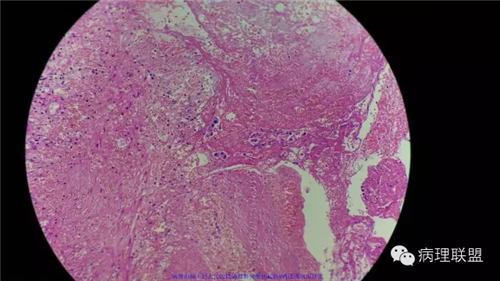

病例1

病史

男性,46岁。慢性胆囊炎急性发作。

(注:病例由禄丰县人民医院病理科吴美仙提供 致谢!)